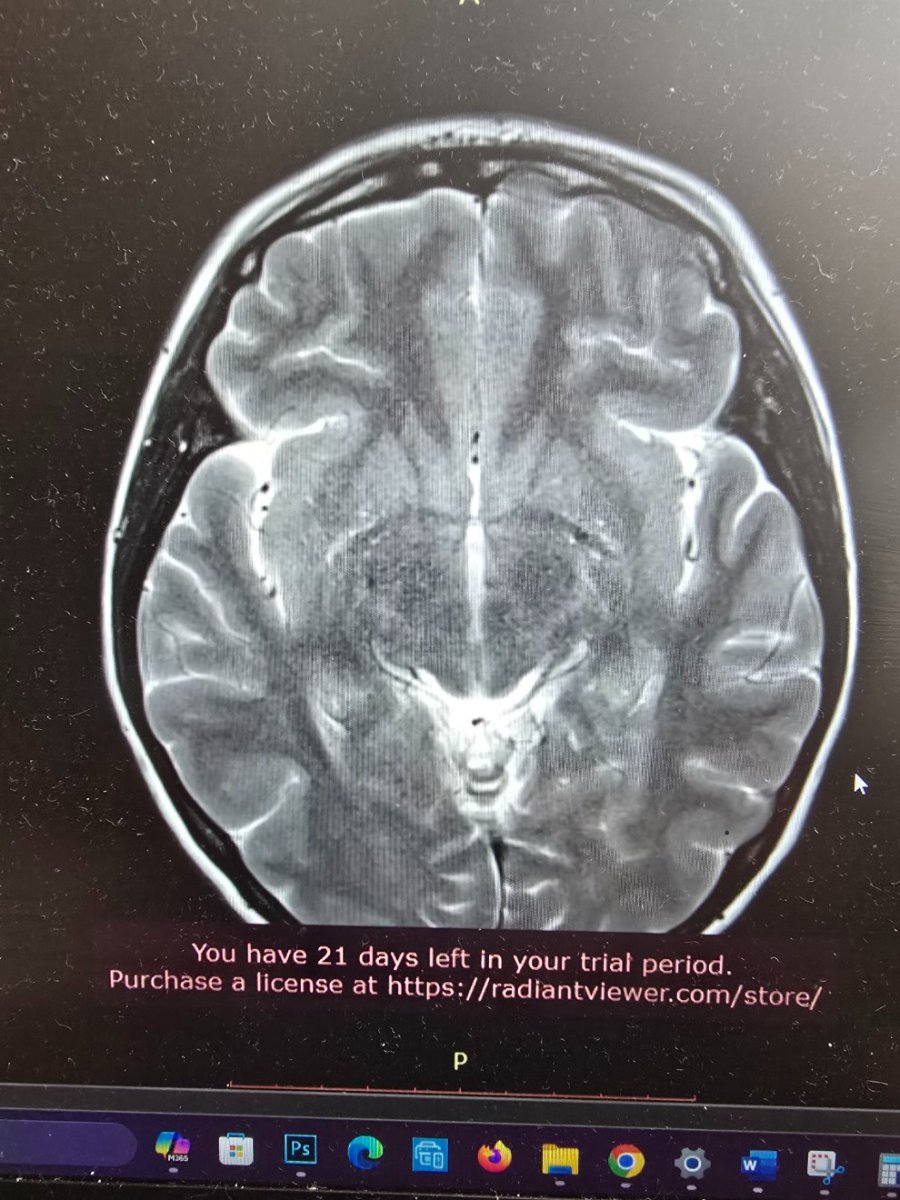

Здравствуйте. Я внимательно посмотрела ваши снимки и описание. Вы уже проделали большую работу — прошли операцию, несколько специалистов и целый комплекс обследований. По МРТ головного и спинного мозга ничего угрожающего нет. Опухолевых или сосудистых изменений не обнаружено. Небольшой «сиринкс» в шейном отделе — это, скорее всего, лёгкое расширение центрального канала спинного мозга. Подобные находки встречаются нередко и чаще всего не несут опасности. Их просто наблюдают раз в год-два, чтобы убедиться, что они не увеличиваются. Поводов для паники нет. Во-вторых, ваши жалобы — чувство «окаменения» головы, боли в шее, тяжесть, головные боли — могут быть связаны с мышечно-тоническим напряжением в шейно-затылочной зоне, которое нередко возникает на фоне остеохондроза, стрессов и гормональных перестроек (в том числе после удаления щитовидной железы). Такие ощущения могут быть очень выраженными и мешать нормальной жизни, хотя причина чаще функциональная, а не структурная. Что сейчас целесообразно сделать: Проверить уровень ТТГ, свободного Т4, кальция и витамина D. После удаления щитовидки важно держать гормональный баланс под контролем. Даже небольшое отклонение может вызывать утомляемость, тревогу, мышечные спазмы и колебания настроения. Сдать ферритин и витамин B12. Дефициты этих веществ часто вызывают слабость, головокружение и ощущение «тумана» в голове. Разобраться с лимфоузлами. Реактивное увеличение до 15 мм на фоне частых воспалений — это чаще следствие хронических очагов (например, миндалин или пазух). Стоит сделать общий анализ крови, С-реактивный белок и обратиться к ЛОР-врачу, чтобы исключить затянувшуюся инфекцию. Для шейного отдела: подойдёт курс мягкой физиотерапии — магнитотерапия, электростимуляция, лечебная гимнастика, релаксирующий массаж. Иногда добавляют препараты с магнием или миорелаксанты, но это решается очно с неврологом. Избегайте агрессивных мануальных воздействий. После операции на щитовидке и при шейных изменениях любые резкие манипуляции противопоказаны. Лучше работать с реабилитологом, который владеет мягкими техниками. Психоэмоциональный компонент. После пережитой операции и постоянных обследований нервная система часто находится в повышенном напряжении. Это естественно. Здесь помогают дыхательные техники, прогулки, нормализация сна и, если необходимо, курс мягких седативных средств по назначению врача. В целом ситуация контролируемая. Сейчас важно не искать у себя опасную болезнь, а постепенно восстанавливать баланс — гормональный, мышечный и эмоциональный. Если хотите, я помогу вам составить поэтапный план восстановления — с обследованиями, питанием, физической активностью и поддерживающими методами. Хотите, чтобы я сделал такой план? ⚠ Важно: Согласно законодательству РФ (ст. 70 Федерального закона № 323-ФЗ «Об основах охраны здоровья граждан в Российской Федерации»), назначение лекарственных препаратов возможно только после очного осмотра врача и установления диагноза. Поэтому приведённые рекомендации не являются индивидуальным назначением, а представляют собой обобщённые терапевтические подходы, применяемые в аналогичных клинических ситуациях. Для точного подбора терапии и исключения противопоказаний необходимо обратиться к врачу очно.

Добрый день всем. Мне 37 лет. 1 года назад удалили щитовидку. По показания (фоликулярный неоплазия, оказалось аденомой). После этого у меня постоянно выполнение лимфатических узлов, и гнойные инфекции они и раньше были.1 недели опухают потом отпускают и опять заново, Я пошла на узи там 2.2см. Отправили к Орл, пока дошла очередь лимфатические узлы уменьшились. Тот отправил делать Мрт. (На Мрт шейного отдела, лимфо узлы 15 млм, и Диски позвонков ранние дегенервтивные изменения, и маленький сиринкс позвонка Т2. Других аномалий не нашли. Головные боли усилилисьи постояннов сердце екала . Я уже к неврологу за таблетки тот прописал успоительные, (то я кажусь ему в стрессе) и отправил меня уже на энцефелограму, там А ритм 8-9 Гц нестабилен, и Интерференция периодических медленных θ -волн без явных очагов. Потом отправил меня к Неурохирургу, тот дал направление на Мрт головы. На мрт головы всё чисто ничего не нашли. У меня голова как будто замороженная, или твердеет окаменеет, даже не знаю как объяснить. Периодически боли с передней шеи где постоянно чувствую там то ли гланды болят какие-то то-ли лимфо...и задняя часть шею болит тоже. Массаж, холодный душ, киропрактик помогает временно. Вес у меня 70кг при росте 159 см. Занимаюсь ходьбой